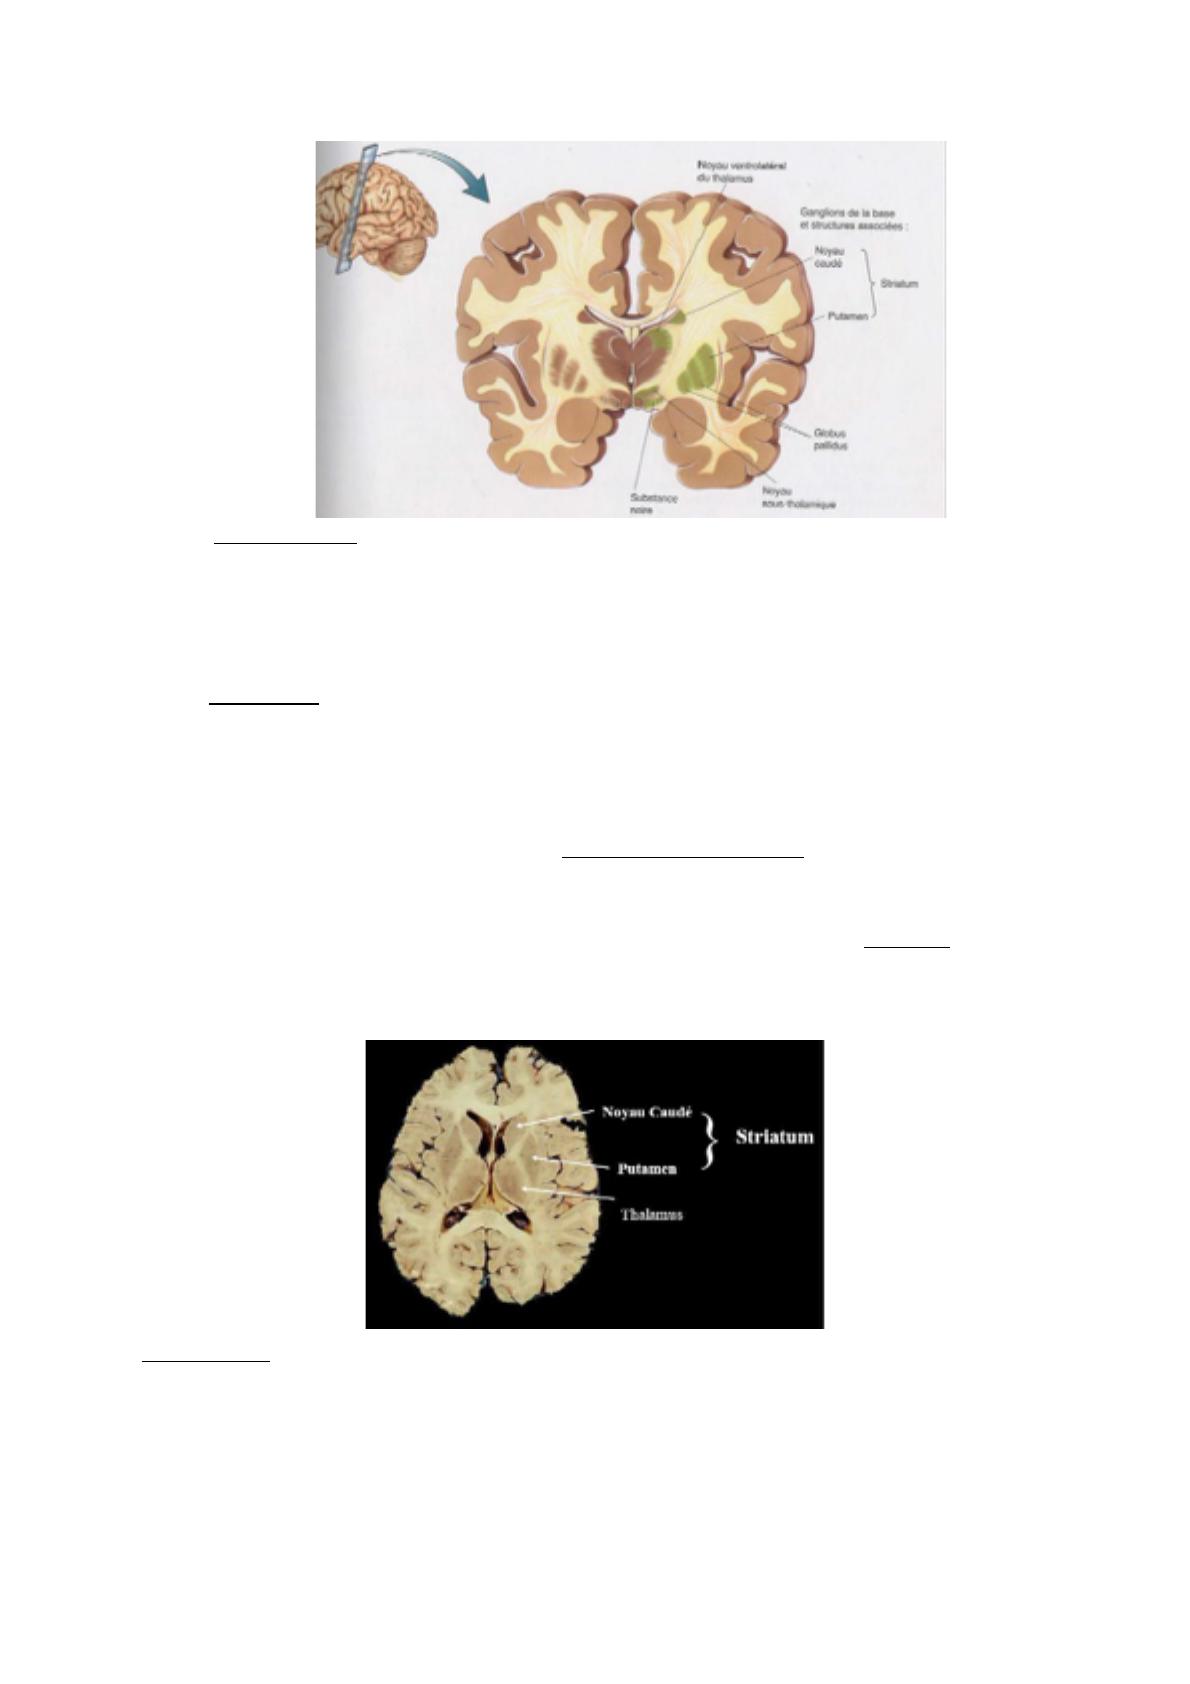

Les ganglions de la base sont formés du :

- STRIATUM (2 structures = putamen + noyau caudé),

- GLOBUS PALLIDUS (2 structures = interne et externe),

- NOYAU SOUS-THALAMIQUE,

- SUBSTANCE NOIRE.

Coupe coronale : on voit la tête du noyau caudé, le noyau ventral latéral du thalamus, les

noyaux lenticulaires avec les 2 globulus pallidus internes. Les consituants du striatum sont le

noyau caudé et le putamen. Entre ces 2 structures, des ponts/connexions qui sont constitués

notamment au niveau de sa partie antérieure. Au-dessous de la capsule interne, le noyau sous-

thalamique et la substance noire (très importante).

Coupe axiale : le noyau caudé esten regard de la corne frontale. Le putamen est la structure

la plus externe. Le globus pallidus interne est en regard du genou de la capsule interne.